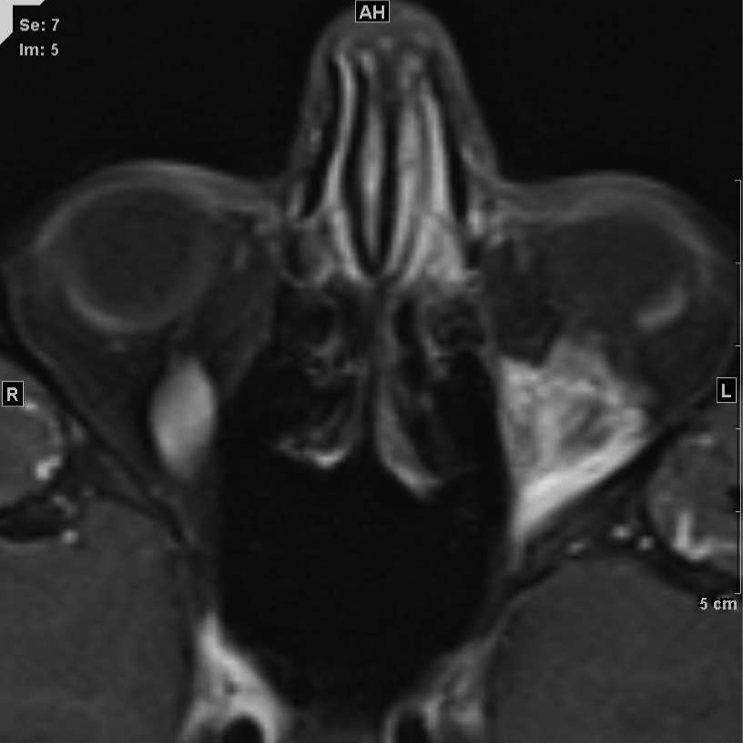

MRI of large LM cyst (top), catheter passing through lower lid (left), cystogram (right).

MRI of small LM cysts (top), US of needle injecting individual cysts (left), photo of US guided technique for small cyst puncture (right).